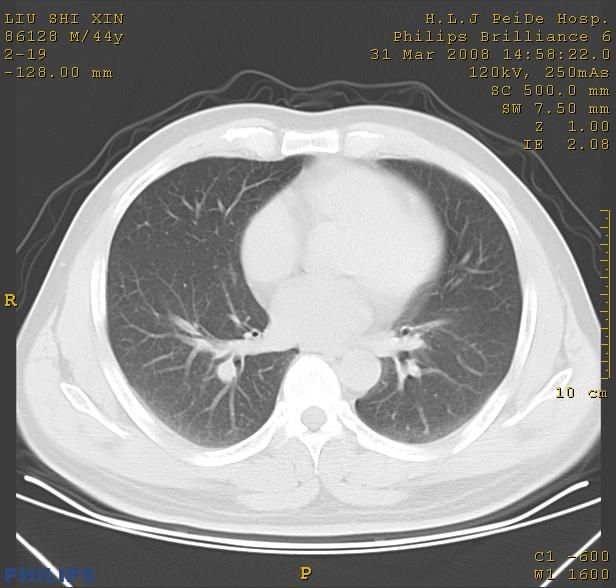

标题: CT13096:请分析胸膜下结节的影像基础是什么 有病理结果 [打印本页]

标题: CT13096:请分析胸膜下结节的影像基础是什么 有病理结果

考虑右上叶慢性炎症可能性大,不完全除外肺癌。

瘢痕挛缩,胸膜牵拉,血管纠集扭曲,上叶前段支气管显示欠清,周围散在斑片影,以纵隔旁肺癌可能性大。请穿刺检查。

中心型肺癌并阻塞性肺炎及肺内转移

中心型肺癌并阻塞性肺炎、两肺及胸膜多发转移。

本病例有病理结果是,鳞状上皮癌,胸膜下结节影病现诊断的肿大淋巴结,谢谢大家分析,请问胸膜下结节是肿大淋巴结怎么解释